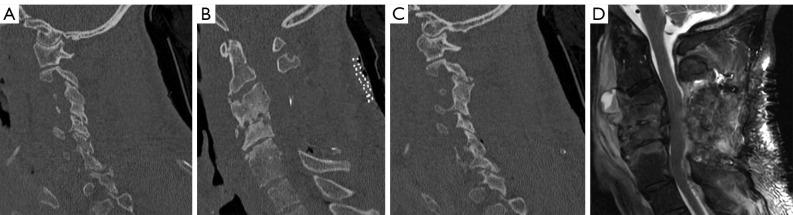

Case description: We present a medically complex 58-year-old male who developed a severe combined kyphotic and coronal cervical deformity in a delayed fashion after an initial posterior cervical decompression for symptomatic epidural abscess associated with VO. The patient underwent a combined two-stage anterior and posterior approach. The patient tolerated both surgeries without complication and follow-up imaging demonstrated correction of cervical sagittal and coronal alignment. Interestingly, despite appropriate antibiotic therapy, intraoperative culture during deformity correction yielded growth of the initial culprit microorganism.

Conclusions: A two-stage anterior and posterior approach with multi-level anterior cervical decompression and instrumented fusion followed by posterior cervicothoracic instrumented fusion addresses the primary surgical goals of affected spinal segment decompression, restoration of appropriate spinal alignment, and prevention of further deformity or neurologic compromise. This report highlights suitability of techniques accessible to most spinal surgeons for correction of a multiplanar deformity, contributes to the ongoing discussion regarding instrumentation in the setting of an active spinal infection, and emphasizes the importance of close clinical and radiographic follow-up in this patient population.